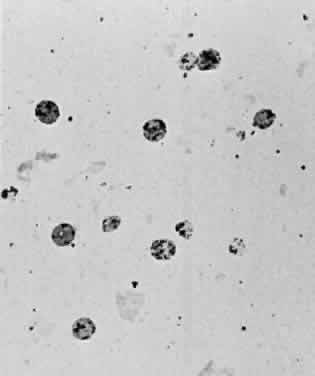

Fig. 53. Trypsin digest of the retinal capillary circulation demonstrating microaneurysm

formation. (Courtesy of Ralph C. Eagle Jr, MD, Philadelphia, PA) Fig. 53. Trypsin digest of the retinal capillary circulation demonstrating microaneurysm

formation. (Courtesy of Ralph C. Eagle Jr, MD, Philadelphia, PA)

|